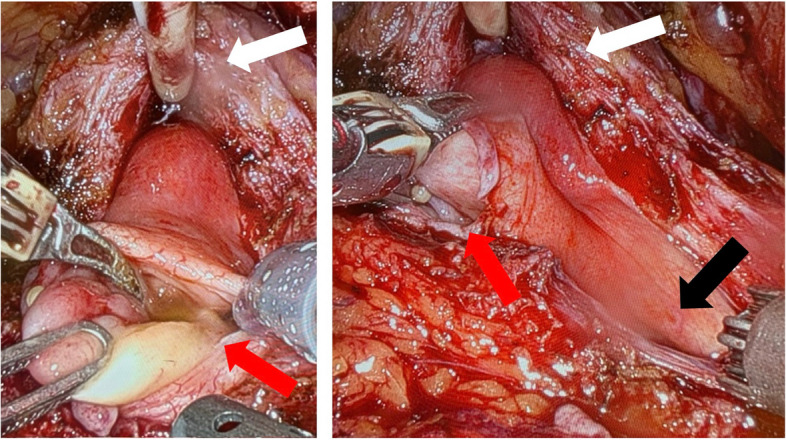

简介和重要性:“先天性肾脏和尿路异常”(CAKUT)是一种异质性和罕见的影响尿路的疾病。尽管超声广泛可用,先天性尿路畸形的诊断往往是在成年。因此,在成像调查中,CAKUT通常是偶然发现的。本病例报告首次描述了同时手术治疗CAKUT和保留神经的前列腺切除术,表明合并手术并不存在缺点,并且在神经安全控制下仍然可以进行成功的保留神经的根治性前列腺切除术。病例介绍:在这个报告中,我们描述了一个前列腺癌患者,他偶然发现左侧CAKUT,包括肾发育不全,输尿管膨出和膀胱憩室。患者同时行保留神经的根治性前列腺切除术、输尿管切除术和憩室切除术。术后第10天拔管后,患者尿控良好(24 h尿垫试验6gr,排尿量450 ml,无残尿)。病理检查显示pT2c pN0 (0/5) R0, GS 3 + 4 = 7a前列腺腺癌。患者对手术及其结果表示高度满意。结论:该病例首次表明,结合上、下泌尿生殖道的复杂手术,考虑肿瘤因素,可以安全地进行,而不会影响早期功能或早期肿瘤预后。

INTRODUCTION AND IMPORTANCE: "Congenital anomalies of the kidney and urinary tract" (CAKUT) represent a heterogeneous and rare group of disorders affecting the urinary tract. Despite the widespread availability of ultrasound, the diagnosis of congenital urinary tract malformations is often made in adulthood. As a result, CAKUT are typically incidental findings during imaging investigations. This case report represents the first description of a simultaneous surgical therapy of CAKUT and nerve-sparing-prostatectomy, demonstrating that concomitant surgery does not present disadvantages and that a successful nerve-sparing radical prostatectomy can still be performed under NeuroSAFE control. CASE PRESENTATION: In this report, we describe a patient with prostate adenocarcinoma who had an incidental finding of left-sided CAKUT, including kidney aplasia, ureterocele, and bladder diverticulum. The patient underwent a simultaneous nerve-sparing radical prostatectomy, ureterectomy, and diverticulectomy. After catheter removal on day 10 after surgery, the patient demonstrated adequate continence (6gr in 24 h pad test, 450 ml voiding volume, no residual urine). The pathological examination revealed a pT2c pN0 (0/5) R0, GS 3 + 4 = 7a adenocarcinoma of the prostate. The patient expressed high satisfaction with the surgery and its outcomes. CONCLUSION: This case demonstrates for the first time that a combined approach to complex surgeries of both the upper and lower genitourinary tracts, addressing oncological considerations, can be performed safely without compromising early functional or early oncological outcomes.